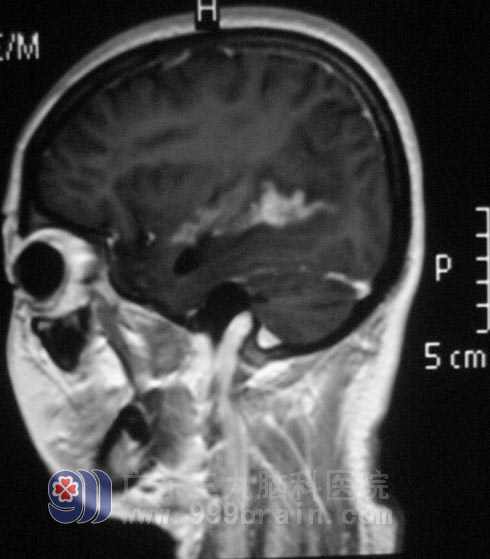

去年10月,陈女士开始出现头痛、头晕,她和家人都没有在意。一个月后,头痛症状加重,伴恶心、呕吐,当地医院头颅MR检查提示右侧脑室多发占位。陈女士曾经感染过梅毒,医生考虑为梅毒肉芽肿,给予对症治疗后头痛症状好转。

今年年后复查头颅MR提示右侧脑室占位较前增大,因占位性质难以确定,当地医生不敢贸然手术。

广东三九脑科医院综合神经外科 鲁明主任详细了解病史及阅片后,考虑为颅内寄生虫,病变部位主要位于功能区;脑脊液寄生虫检查也提示:裂头蚴抗体IgG弱阳性。http://www.999brain.com/

▲手术前